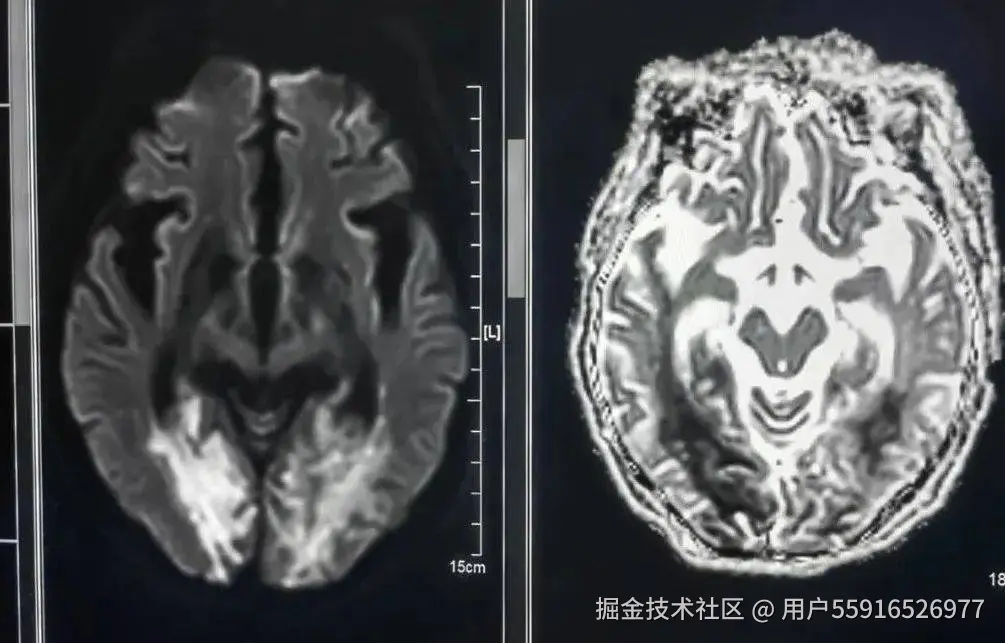

非增强性脑血管成像(MRA)

MRA是一种无创、无辐射、简便经济、精准的脑血管筛查方法,相较脑血管CT三维重建(CTA)和脑血管造影(DSA)则需要注射造影剂,在X射线下辅助完成检查,二者只在进一步确诊脑血管疾病时考虑使用。